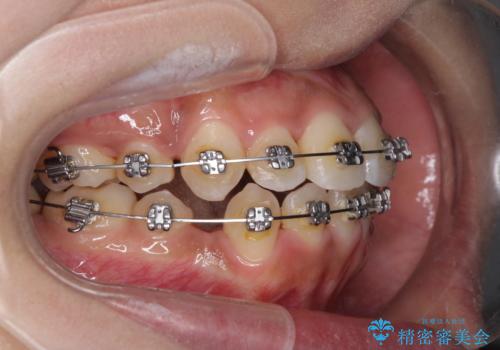

- メタルブラケット

- 2年1ヶ月

- 10-30回

上下の正中位置が大きくずれていたため、治療期間の長期化や正中が合わないまま終了することが予想されましたが、思っていた以上にスムーズに歯が移動し、満足いただける仕上がりとなりました。